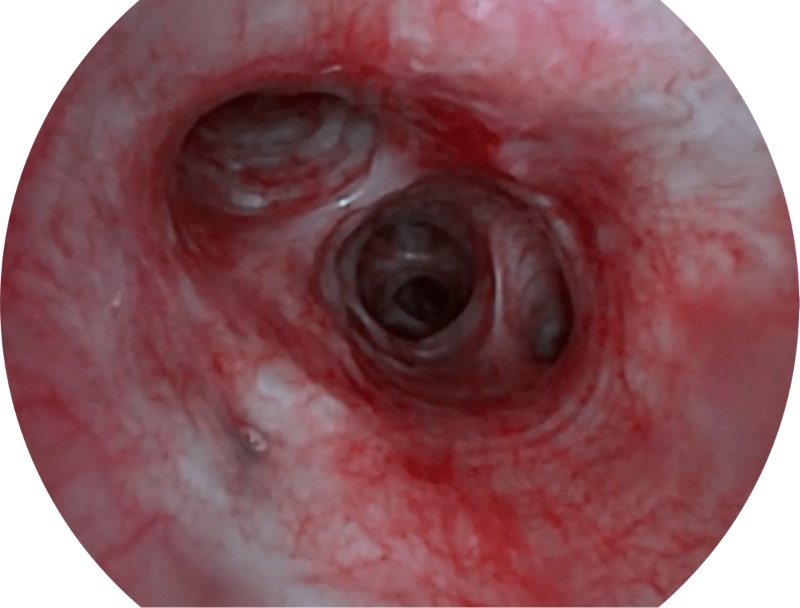

SFI